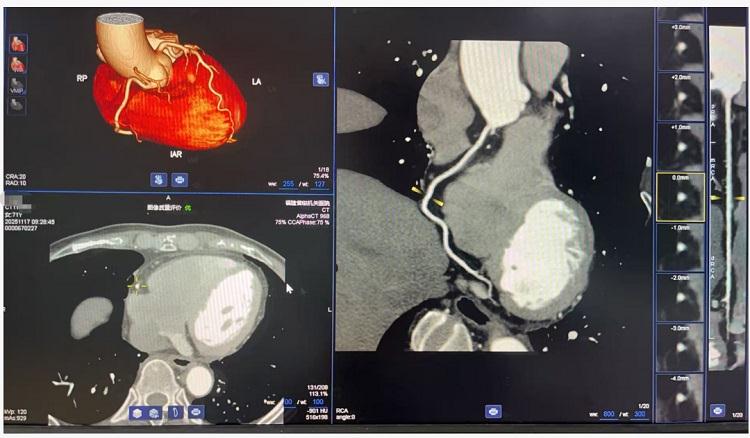

在臨床應(yīng)用方面,256排螺旋CT展現(xiàn)出廣泛的適用性。設(shè)備可完成冠狀動(dòng)脈、頭頸部血管的無(wú)創(chuàng)成像,清晰顯示血管狀況,為心腦血管疾病的早期篩查與診斷提供重要依據(jù)。在腫瘤診療領(lǐng)域,通過(guò)先進(jìn)的三維重建技術(shù),能夠清晰呈現(xiàn)病灶細(xì)節(jié),助力腫瘤精準(zhǔn)分期和治療方案制定。特別是在急診急救方面,設(shè)備可快速完成多部位聯(lián)合掃描,為胸痛、外傷等急癥患者爭(zhēng)取寶貴的救治時(shí)間。

冠狀動(dòng)脈CTA檢查成像